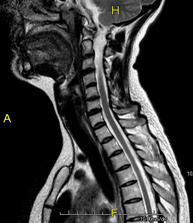

- Cervical spine MRI

This non-invasive diagnostic procedure uses an electromagnetic field and radio waves (from a transmitter and receiver) to acquire high-definition anatomical images of the cervical spine. It is a radiation-free procedure. Indicated for: trauma, spinal degeneration, hernias.